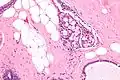

Micrograph of collagenous spherulosis with the characteristic histomorphology - intratubular eosinophilic material with a spoke-like arrangement. H&E stain.

Collagenous spherulosis is characterized by a tubular/cribriform architecture with intratubular eosinophilic material that classically is arranged like the spokes of a wheel ("radial spikes"). There is usually no mitotic activity, and two cells populations (epithelial & myoepithelial) are present, like in benign breast glands.

The lesions are typically small (less than 50 spherules per lesion, less than 100 micrometers in size) and may be multifocal.